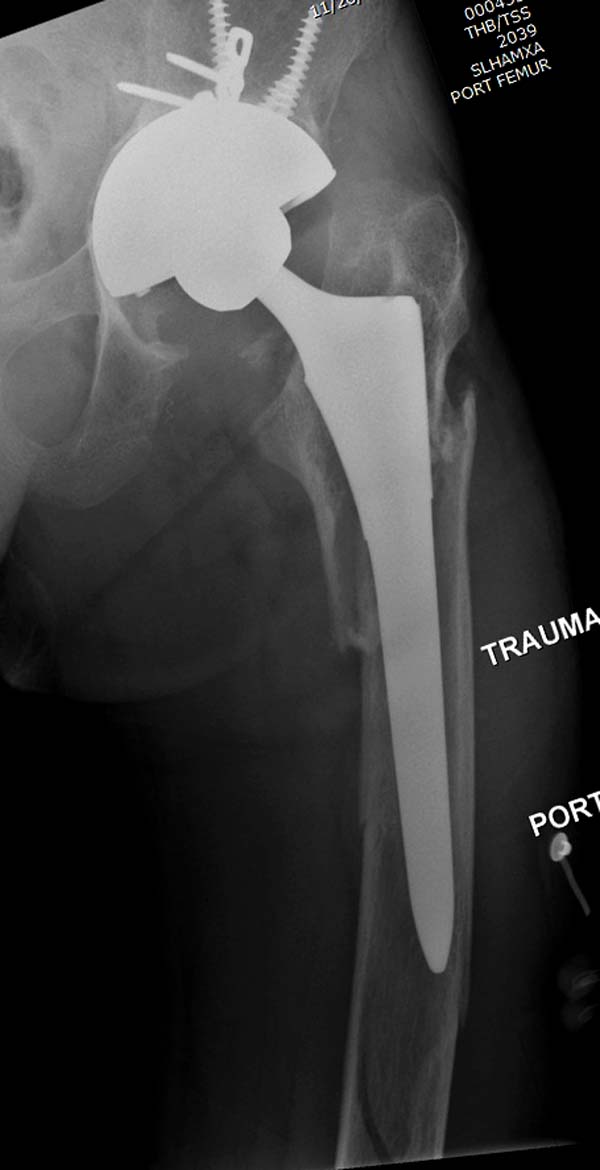

Больному 25 лет, транспортная травма. С детства хроническая почечная

недостаточность, постоянный гемодиализ, находится в листе ожидания на

пересадку почки. Около 4 года назад автоавария с двухсторенним переломом

ацетабулум, которая слева закончилось тотальным протезированием.

Диагноз: переломы бедренных костей, перелом дистального плеча слева,

также неосложненный перелом на уровне грудных позвонков.

Рентген снимки. Хотели услышать примерный алгоритм лечения, c чего

начать и как?

Имя     : 5 Periprosthetic IM nail Lt femur 3.jpg